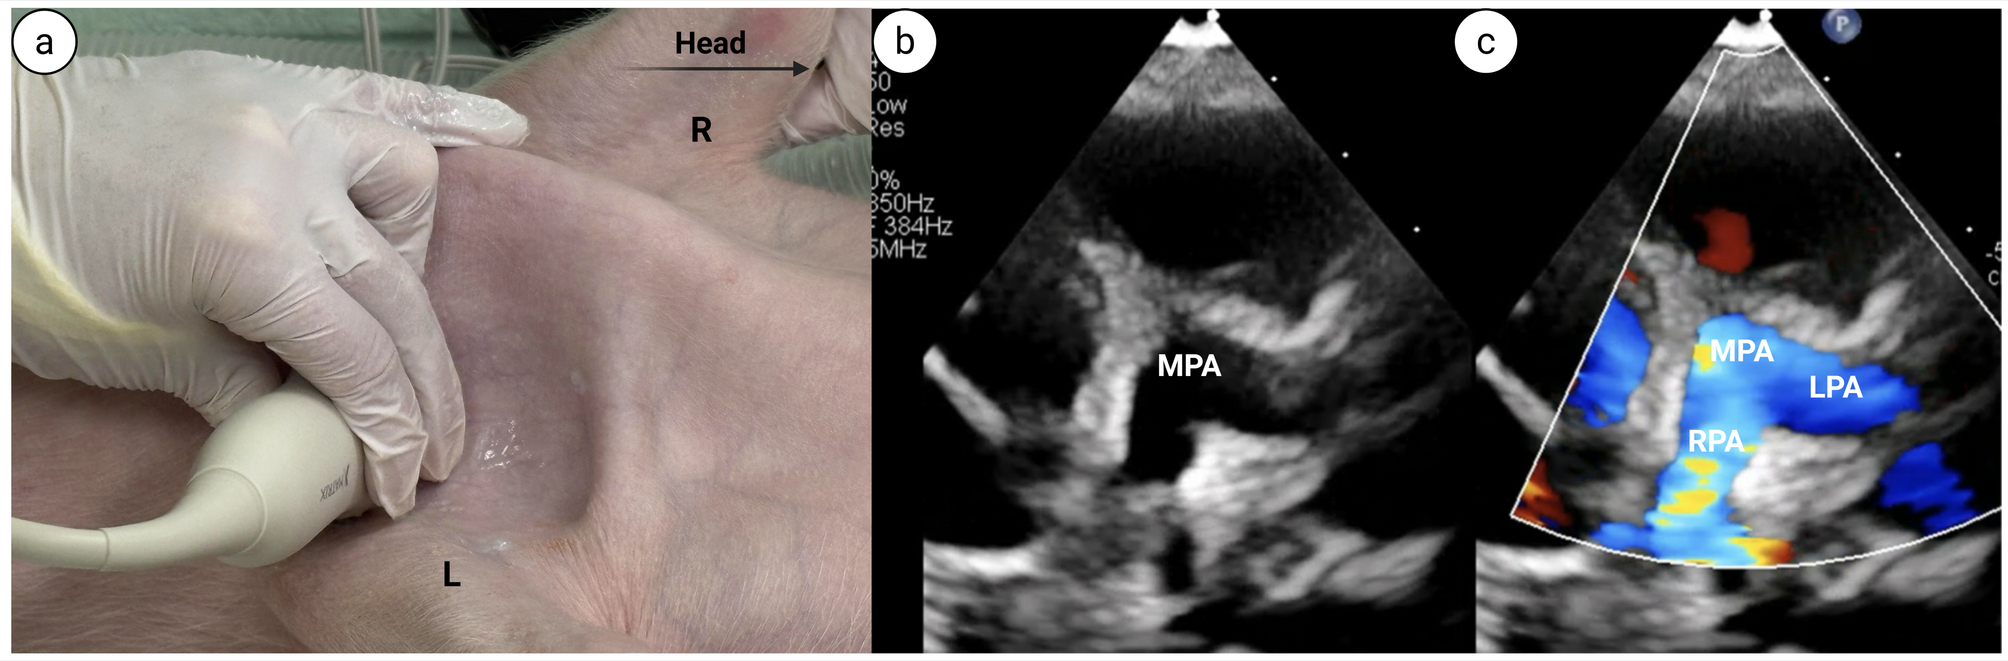

Patent ductus arteriosus (PDA) view.